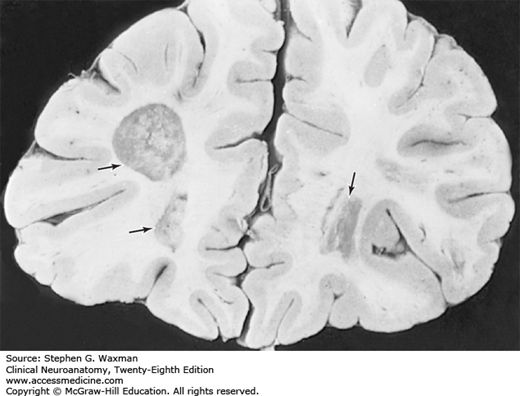

Areas of demyelination of the white matter (arrows) in the frontal lobe of a 54-year-old man with multiple sclerosis.